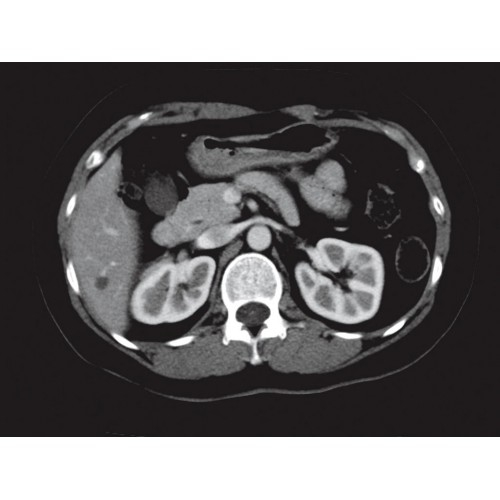

Позволяет проводить комплексные исследования всех анатомических зон, включая нейровизуализацию, ангиографию, исследования органов грудной и брюшной полости. Особенно эффективен для раннего выявления онкологических заболеваний.